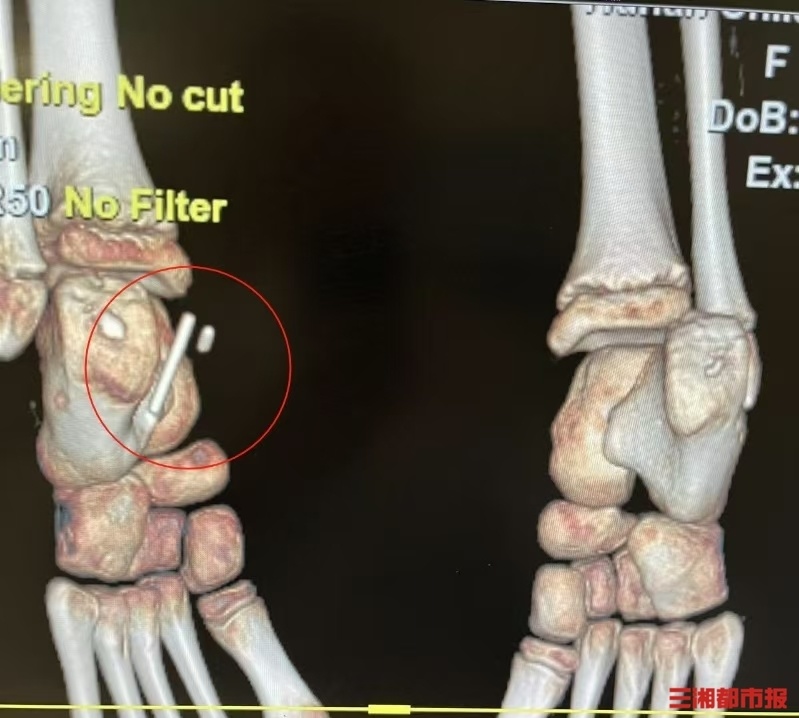

三湘都市报3月24日讯(全媒体记者 高煜棋 通讯员 乔木 吴丽霞)8岁女孩刘彤彤(化名)在自家沙发上蹦跳,结果不慎踩到铅笔,扎进脚底。伤口发展到慢性跟骨骨髓炎,在湖南省儿童医院实施了高难度异物取出术,取出贯穿神经血管束的铅笔芯及深部异物。

可过了一段时间,刘彤彤左踝内侧突发红肿包块伴压痛,反复换药仍不见好,还形成了局部窦道,反复流血。刘玲将女儿带到湖南省儿童医院骨科后,经完善X线、CT、MRI等检查,确诊为左跟骨慢性骨髓炎,伤口中还发现了异物。刘玲这才恍然:“当时彤彤说不见了的铅笔,居然还留在她的脚里面。”

省儿童医院骨科创伤团队在全麻下为彤彤实施“左跟骨骨髓炎病灶清理+VAC引流术+异物探查取出术”。术中发现彤彤内踝窦道深部嵌有1.5毫米×10毫米的黑色铅笔芯,重要血管神经深部还发现一截3厘米长的完整铅笔。医院骨科主任医师伍江雁表示,彤彤的手术难度不小,异物位置深,探查定位困难,且毗邻神经血管,术中极易损伤血管神经,且术后还要预防感染,避免骨骼畸形和肢体缩短等并发症。